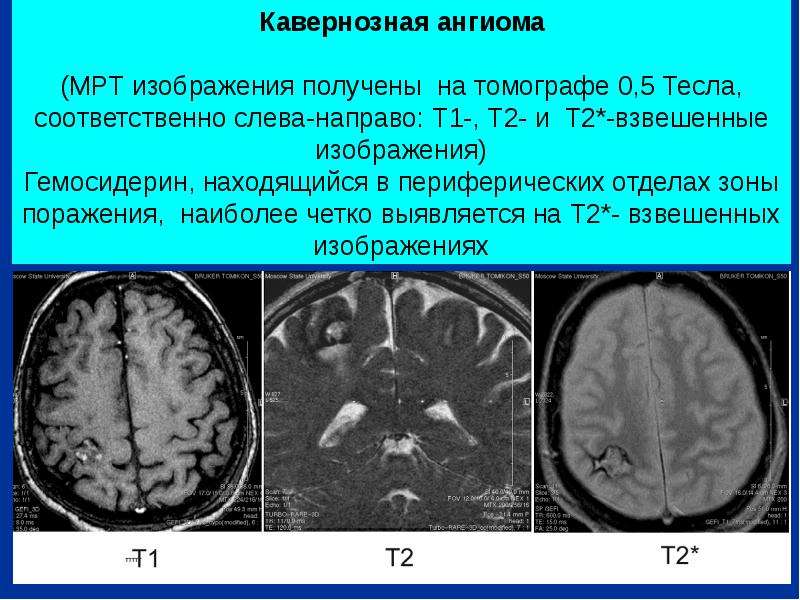

Мр картина венозной ангиомы левой гемисферы мозжечка - 96 фото